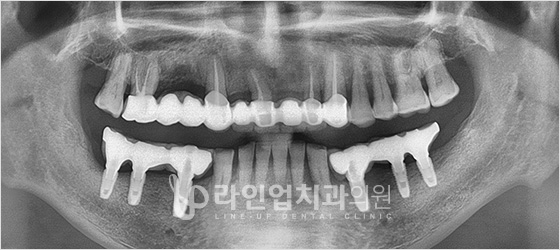

Before

After

Имплантация верхних моляров